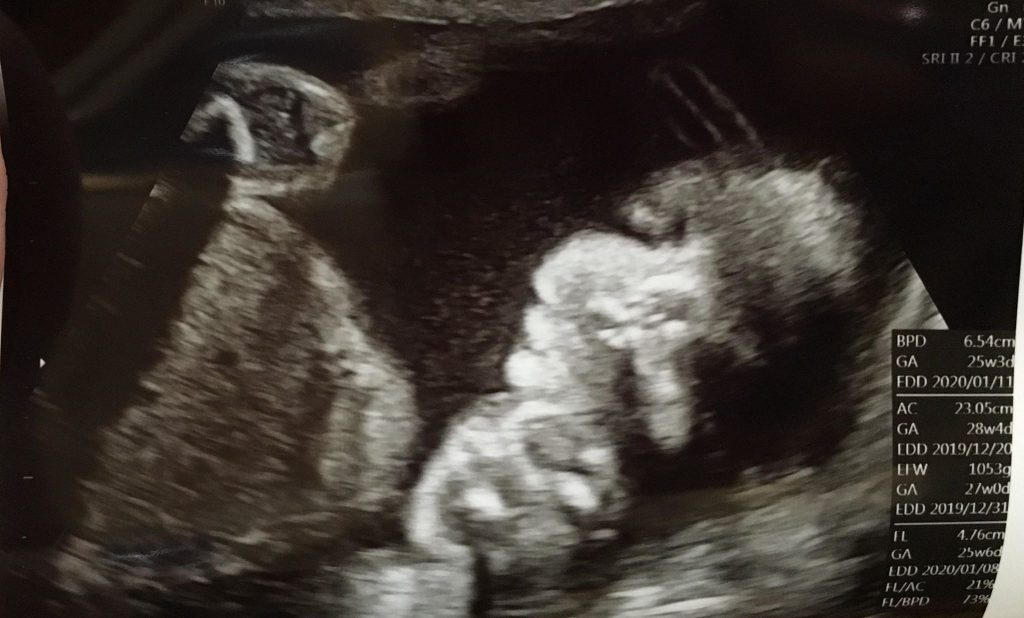

在等待的過程也安排了例行性的產檢,利用空檔時間來看一下阿飽妹的成長狀況,果然是個頭好壯壯成長快速的寶貝,還被醫生說:「妳媽媽把你養的太大了啦~」,因為整整超前了200多克左右雖然第一胎也是壯壯系列的,但這胎似乎更驚人!!!天啊~我還想要自然產呢?不過,心想健康最重要,就先別去想了吧~哈哈!!